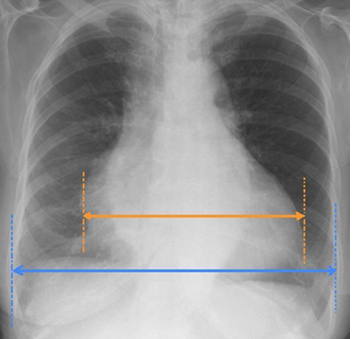

Cardiac size

is measured by drawing vertical parallel lines down the most lateral points of the heart and measuring between them.

Thoracic width

is measured by drawing vertical parallel lines down the inner aspect of the widest points of the rib cage, and measuring between them

Cardiothoracic Ratio (CTR)

is frequently expressed as a percentage.

Abnormal

A CTR of greater than 1:2 (50%) is considered ___

Accurate assessment of heart size assumes the projection is PA and that cardiac size is not exaggerated by factors such as patient rotation